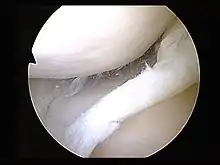

The tear of meniscus is among the most common knee injuries. It is usually caused by torsional stress; twisting or turning of the knee too quickly with the foot planted on the ground while the knee is flexed. The feeling of a "pop" in the knee is usually felt when the meniscus is torn. Athletes, particularly those who participate in contact sports, are at a greater risk for meniscal tears. Sports-related meniscal tears often occur with other knee injuries, such as an anterior cruciate ligament tear.

A torn meniscus is commonly referred to as torn cartilage in the knee. Menisci tear in different ways and are noted by how they look, as well as where the tear occurs in the meniscus. Two types of tears include minor, which includes stiffness and swelling within two to three days but usually goes away in two to three weeks. Then there is severe, which without treatment, a piece of meniscus may come loose and drift into the joint space. Tears include longitudinal, parrot-beak, flap, bucket handle, and mixed/complex.

Treatments For Unhappy Triad Injury

Treatment of the unhappy triad usually requires surgery. An ACL surgery is common and the meniscus can be treated during the surgery as well. The MCL is rehabilitated through time and immobilization. Physical therapy after the surgery and the use of a knee brace help speed up the healing process. A typical surgery for a blown knee includes:

- Patellar tendon autograft (An autograft is a graft that comes from the patient)

- Hamstring tendon autograft

- Quadriceps tendon autograft

- Allograft (taken from a cadaver) patellar tendon, Achilles tendon, semitendinosus, gracilis, or posterior tibialis tendon

The goal of reconstruction surgery is to prevent instability and restore the function of the torn ligament, creating a stable knee. There are certain factors that the patient must consider when deciding for or against surgery.